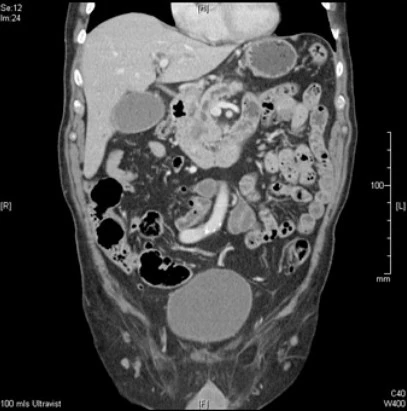

4. 복부 CT(전산화 단층촬영)

이 암의 병기를 진단하고 측정하는 데 초음파보다 더 유용합니다. 검사자에 의한 오차가 적고 병변을 객관적으로 관찰할 수 있으며 영상이 보다 상세하여 1cm 정도의 종양도 검출이 가능합니다. 암의 병기 결정에 필수적이므로 황달이 있는 노인 환자 중 췌장암이 의심되는 경우 CT를 먼저 시행하게 됩니다.

특히 다중검출 나선형 전산화 단층촬영은 췌장암 진단률을 크게 높였습니다. 영상 획득 시간이 짧기 때문에 인체를 여러 개의 얇은 단면으로 절단하여 한 번 숨을 참으면서 관찰할 수 있으며, 병변이 더 잘 보이도록 영상 시간을 조절할 수 있어 췌장에 대한 명확한 진단이 가능합니다. 더 나아가 수술의 가능성을 높여줍니다.

또한 판단을 위한 정확한 데이터를 제공하기 때문에 진단을 위해서는 초음파보다 먼저 나선형 전산화 단층촬영을 시행하는 것이 좋습니다.